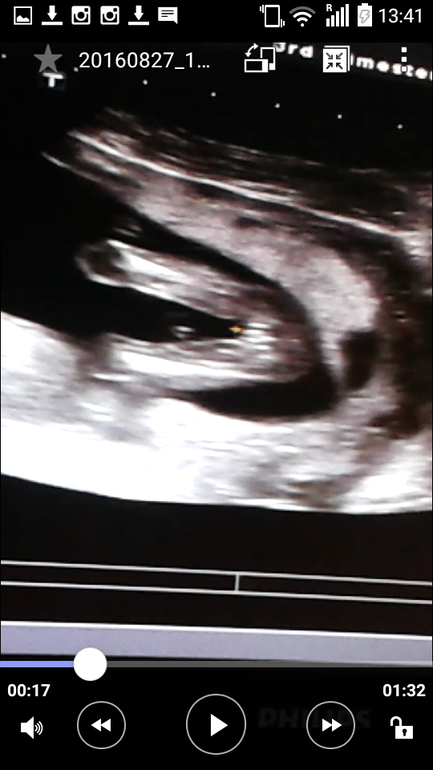

Ждём девочку)))))

Вертится с трудом, но видно всё было четко. Несколько раз поймали ракурс и все рассмотрели.

между ножек: